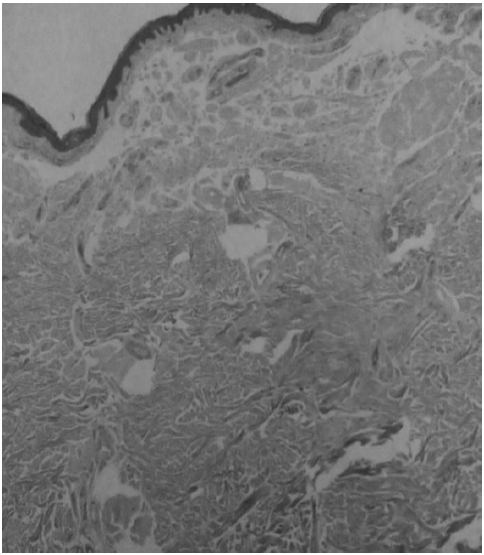

Гистологическое исследование: эпидермис утолщен с акантозом и гиперкератозом. Субэпидермально определяется скудная периваскулярная лимфогистиоцитарная инфильтрация. В дерме фрагментация коллагеновых волокон. При окраске на конго рот – позитивная реакция. Заключение: амилоидоз кожи (рис. 2).

Рис. 2. Гистологическая картина амилоидоза кожи

Амилоидоз кожи дифференцируют с веррукозным красным плоским лишаем, микседематозным лихеном, лишаем Видаля, узловатой почесухой Гайда, бородавчатым туберкулезом кожи, поствоспалительной гиперпигментацией [3, 6]. Диагноз устанавливают на основании клинических и гистологических (включая гистохимические) данных. Гистологическая картина локализованного кожного амилоидоза характеризуется отложением амилоида в дерме, вокруг сосудов, выводных протоков сальных и потовых желез, волосяных фолликулов в виде аморфных розовых (при окрашивании гематоксилином и эозином) глыбок или кристаллов, более крупных при узловато-бляшечном варианте. Вокруг них располагается умеренное количество фибробластов и плазматических клеток. Воспалительной реакции, как правило, нет, лишь иногда обнаруживают незначительный периваскулярный лимфоцитарный инфильтрат. Эластические волокна в местах отложения амилоида отсутствуют. В эпидермисе определяется акантоз и гиперкератоз [8, 13, 14]. Также используют специальные методы, в том числе исследование в поляризационном микроскопе после окрашивания конго рот, молекулы которого откладываются и выравниваются перпендикулярно продольной оси амилоидных фибрилл, заметно увеличивая их анизотропию и проявляясь в виде светло-зеленого двойного лучепреломления [7, 10].